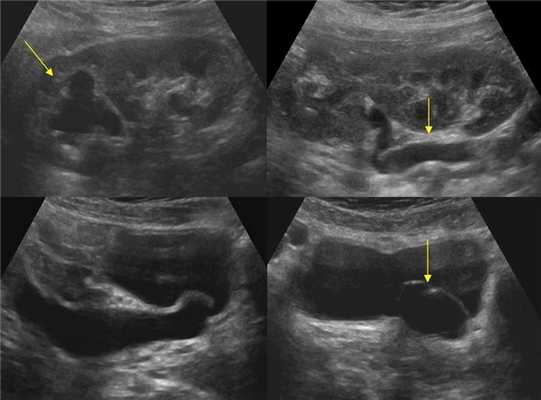

Рисунок. При полном удвоение почки каждая из половин имеет самостоятельную лоханку и мочеточник, который открывается в мочевом пузыре самостоятельным устьем. При этом они дважды между собой перекрещиваются: на уровне нижнего полюса почки и в малом тазу. Устье мочеточника нижней половины в мочевом пузыре располагается выше устья мочеточника верхней половины (закон Вейгерта-Мейера). Уретероцеле, мегауретер и гидронефроз верхнего сегмента полноудвоенной почки; нижний сегмент почки не страдает.

- Степень 1: небольшое уретероцеле с незначительными изменениями верхних мочевых путей — чаще затронут только верхний полюс удвоенной почки;

- Степень 2: крупное уретероцеле со значительными изменениями верхних мочевых путей — пострадали оба сегмента удвоенной одной почки;

- Степень 3: страдают обе почки — двусторонний уретерогидронефроз.

Рисунок. У новорожденного на УЗИ почек определяется гидронефроз (1) и расширенный мочеточник (2) справа. В мочевом пузыре двустороннее уретероцеле (3). При исследовании левой почки структурных изменений не выявлено.

Рисунок. На УЗИ определяется удвоенная чашечно-лоханочная система, расширена лоханка верхнего сегмента (1) и мочеточник на всем протяжение (2, 3), в мочевом пузыре уретроцеле (4). Полное или неполное удвоение чашечно-лоханочной системы возможно увидеть с помощью КТ-урографии.

Если обнаружили гидронефроз верхнего сегмента удвоенной почки, должно поискать расширенный мочеточник и уретероцеле.

Иногда расширенный мочеточник или гипоэхогенная матка приподнимают задне-нижнюю стенку мочевого пузыря, тогда ошибочно диагностируют уретероцеле. Обратите внимание, уретероцеле отделено от просвета мочевого пузыря тонкой мембраной, а псевдоуретероцеле — толстой стенкой.